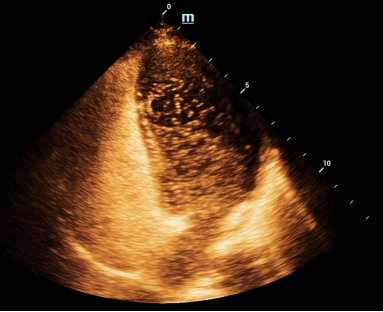

患者,王女士,40岁,因长期头晕、头痛发作,影响睡眠与生活质量,到我院神经内科住院治疗,心脏常规超声检查无特殊发现,但是为了进一步明确病因,神经内科医生为患者申请了我院新技术检查项目——右心声学造影,检查显示多个小“泡泡”从右心房依次进入了左心房、左心室,右向左分流达3级,提示右心声学造影阳性,患者可能存在卵圆孔未闭!

▲右心造影视频

病因终于找到啦,原来这些“小泡泡”在诊断中起到了大用途!